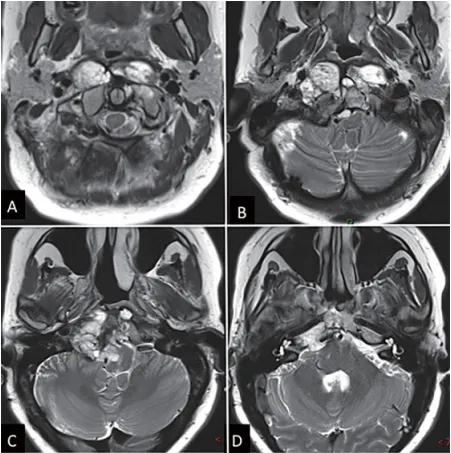

图1显示内镜下鼻内镜入路前的术前影像:(A-D)MRI T2加权成像显示巨大脊索瘤延伸至椎前间隙和齿状突周围。肿瘤横向延伸至舌下管和颈静脉孔,并向内侧延伸至硬膜内间隙。肿瘤从斜坡中部延伸至枢椎齿状突周围。